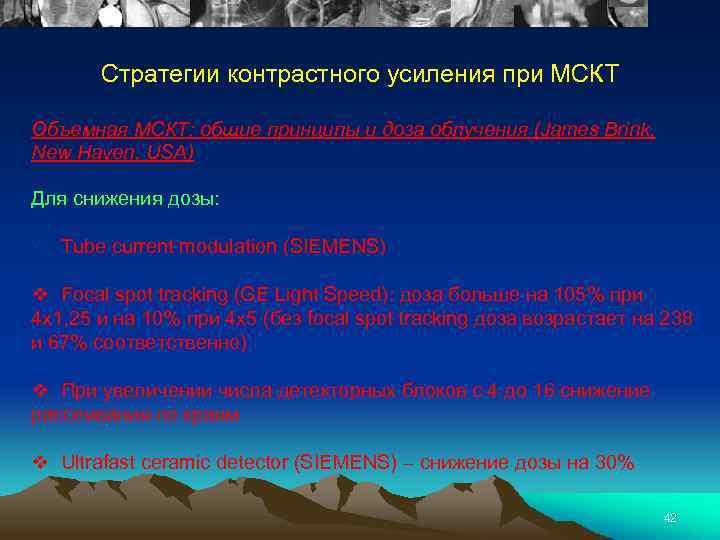

Стратегии контрастного усиления при МСКТ Объемная МСКТ: общие принципы и доза облучения (James Brink, New Haven, USA) Для снижения дозы: v Tube current modulation (SIEMENS) v Focal spot tracking (GE Light Speed): доза больше на 105% при 4 х1, 25 и на 10% при 4 х5 (без focal spot tracking доза возрастает на 238 и 67% соответственно) v При увеличении числа детекторных блоков с 4 до 16 снижение рассеивания по краям v Ultrafast ceramic detector (SIEMENS) – снижение дозы на 30% 42